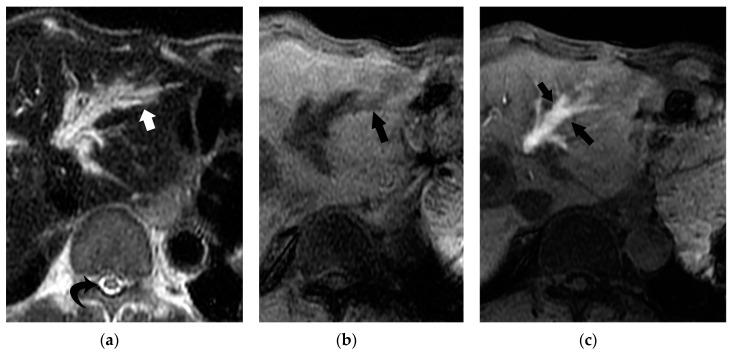

Bile duct necrosis (BDN) with biloma formation is a type of ischemic bile duct injury that is one of the serious complications associated with transarterial therapies, such as transcatheter chemoembolization therapy (TACE), and radioembolization for hepatocellular carcinoma (HCC) and hepatic arterial infusion chemotherapy (HAIC) for metastatic liver cancer from colorectal carcinoma. In terms of the occurrence of BDN and subsequent biloma formation, ischemic injury to the peribiliary vascular plexus (PBP), the supporting vessel of bile duct epithelium, is thought to be intimately associated. In this paper, we first describe the anatomy, blood supply, and function of the intrahepatic bile duct, and then illustrate the pathophysiology of BDN, and finally present the imaging findings of BDN. Under the process of BDN formation, ischemia of the PBP induces the disruption of the bile duct epithelial protection mechanism that causes coagulation and fibrinoid necrosis of the surrounding tissue by the detergent action of exuded bile acids, and eventually a biloma forms. Once BDN occurs, persistent tissue damage to the surrounding bile duct is induced by imbibed bile acids, and portal vein thrombosis may also be observed. On pre-contrast and contrast-enhanced computed tomography (CT), BDN shows similar findings to intrahepatic bile duct dilatation, and, therefore, it is sometimes misdiagnosed. Differentiation of imaging findings on CT and ultrasound (US)/magnetic resonance (MR) imaging/MR cholangiopancreatography (MRCP) is important for correct diagnosis of BDN.

伴有胆汁瘤形成的胆管坏死(BDN)是一种缺血性胆管损伤,是经动脉治疗相关的严重并发症之一,如经导管肝动脉化疗栓塞术(TACE)、肝细胞癌(HCC)的放射性栓塞以及结直肠癌肝转移的肝动脉灌注化疗(HAIC)。就BDN的发生及随后胆汁瘤的形成而言,胆管周围血管丛(PBP)(胆管上皮的支持血管)的缺血性损伤被认为与之密切相关。在本文中,我们首先描述肝内胆管的解剖结构、血液供应和功能,然后阐述BDN的病理生理学,最后介绍BDN的影像学表现。在BDN形成过程中,PBP的缺血会导致胆管上皮保护机制的破坏,渗出的胆汁酸通过去污剂作用导致周围组织发生凝固性坏死和纤维蛋白样坏死,最终形成胆汁瘤。一旦发生BDN,吸收的胆汁酸会导致周围胆管持续的组织损伤,还可能观察到门静脉血栓形成。在平扫及增强计算机断层扫描(CT)上,BDN表现与肝内胆管扩张相似,因此有时会被误诊。CT及超声(US)/磁共振(MR)成像/磁共振胰胆管造影(MRCP)上影像学表现的鉴别对于BDN的正确诊断很重要。